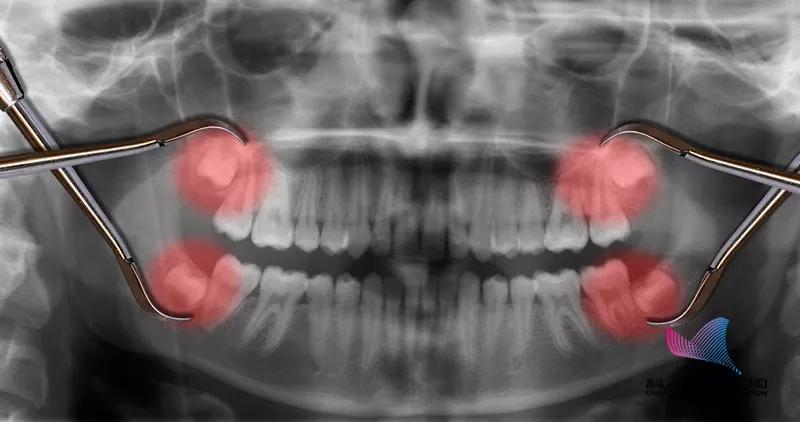

2、长歪的阻生智齿

当智齿没有足够空间生长,脱离“轨道”,与邻牙之间产生缝隙,容易嵌塞食物,滋生细菌,引起蛀牙。

图片来源:作者提供

或是智齿生长的方向正好顶住邻牙,时间久了不仅会把邻牙顶坏,龋坏进一步发展会造成牙髓炎。